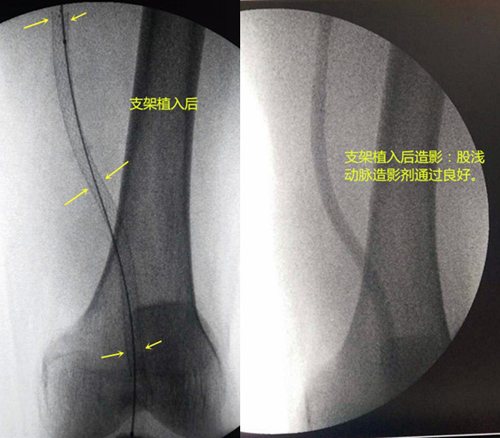

近期,我院放射科在老年综合科及手术室的密切协作下成功开展了“股动脉切开取栓术+股浅—腘动脉球囊扩张+支架植入术+胫前动脉、胫后动脉及腓动脉球囊扩张术”。手术在放射科介入手术室完成;术后在老年综合科赵宗国主任和邓鹏斌医师的精心治疗下最终患肢治愈。此例手术的成功开展关键在于临床能迅速诊断、外周介入能迅速手术及术后能精准治疗的多学科协作的成功案例;同时也填补了我院外周血管腔内成形术的空白,将最大程度的降低我院急性肢体动脉栓塞的截肢率、病死率。

患者入院后,及时开通绿色通道,老年综合科赵宗国主任与邓鹏斌医师积极联系放射科唐小平主任。经两科仔细讨论病情后决定即刻行左侧股动脉切开取栓术。赵主任反复与家属沟通后,在兰大一院介入科专家指导下当晚急诊行“股动脉切开取栓术+股浅—腘动脉球囊扩张+支架植入术+胫前动脉、胫后动脉及腓动脉球囊扩张术”。术中取出最长血栓为11cm(见下图)。

术后第3天,查体:左足第2-4趾皮肤青紫,触之冰凉,患者自诉活动后疼痛加重,考虑缺血时间较长所致,左足第2、3、4趾截肢风险仍较高;左小腿及足背皮肤温度良好,左足背动脉未能触及搏动,左侧胫后动脉搏动良好。